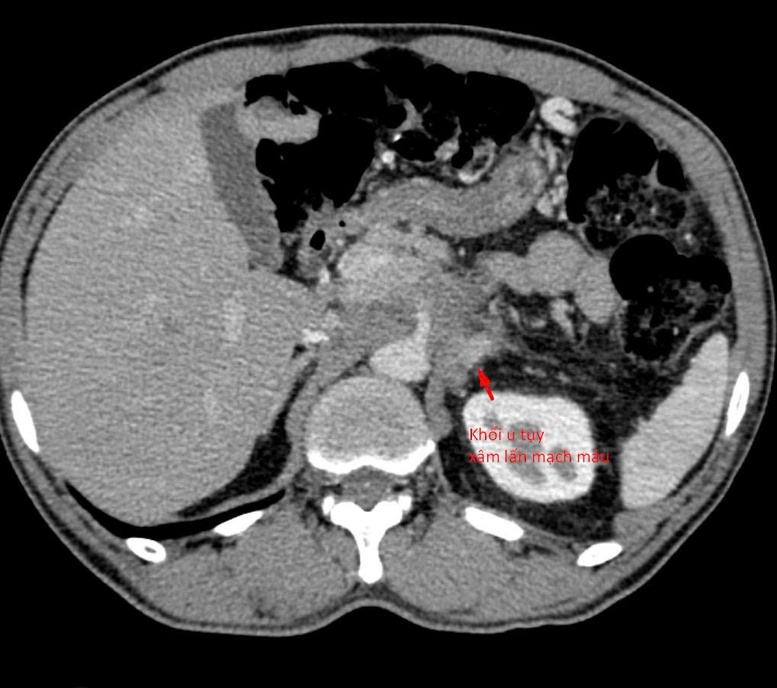

Kết quả chẩn đoán hình ảnh khối u tụy xâm lấn mạch máu của bệnh nhân - Ảnh: VGP

Theo lời kể, sau khi thăm khám tại nhiều cơ sở y tế, người bệnh được phát hiện có khối u tụy xâm lấn mạch máu. Tuy nhiên, do chưa xác định được bản chất khối u, bệnh nhân rơi vào bế tắc trong điều trị. Với tâm lý “còn nước còn tát”, người bệnh đi cầu cúng nhiều nơi, thậm chí tuyệt thực suốt 3 tuần với hy vọng “bỏ đói” khối u.

Theo BSNT Trần Văn Giang, khối u tụy nằm ở vị trí đặc biệt phức tạp, tiếp giáp nhiều mạch máu lớn và các tạng quan trọng, do đó cần xác định chính xác hướng vào an toàn ngay từ đầu. Các bác sĩ đã sử dụng chụp cắt lớp vi tính độ phân giải cao để tái tạo hình ảnh đa mặt phẳng, đánh giá chi tiết mối liên quan giữa khối u và các cấu trúc lân cận, từ đó lựa chọn hướng sinh thiết tối ưu.